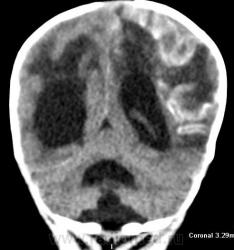

Я думаю, это больше похоже на кровоизлияние - неоднородная структура с гиперденсным компонентом. Плюс ко всему - клиника, судя по всему, с острым началом. Опухоли быстро не растут.

Смущает то, что кровоизлияние как бы в капсуле. А что с извилинами? Пропитывание кровью?

Паразитарная киста - это эхинококк? Образование имеет плотность свежей крови, так что кровоизлияние не вызывает сомнений. Но вот возможно кровоизлияние в опухоль или в результате какой-либо сосудистой патологии, например, ангиоматоза Штурге-Вебера. Насчет течения родов попробую уточнить.

Светлые участки 70 ед Н - плотности крови.

А ведь кровоизлияние есть субарохноидально.

Денди Уокер? Не думаю, хотя надо посмотреть аксиалы ниже уровня намёта. А пока явно вижу признаки Sturge-Weber syndrome - encephalotrigeminal angiomatosis синдром со всеми вытекающими.